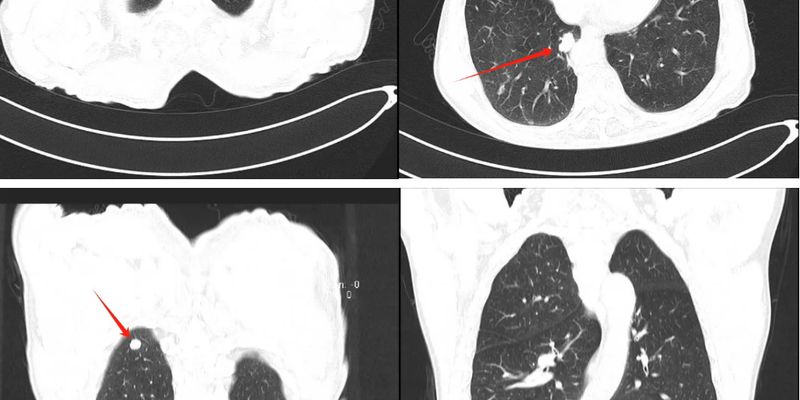

越来越多的人选择全身扫描来寻求健康保障和早期发现疾病。然而,这种看似先进的体检方式,可能带来不必要的健康焦虑、过度诊断,甚至引发一系列的后续检查和治疗。本文将深入剖析全身扫描的真实价值、潜在风险及对医疗系统的影响,帮助您理性看待和选择体检方式,避免盲目跟风,减轻身心负担。 Read More... "全身扫描是福是祸?深度解析“过度诊断”的陷阱与潜在风险"